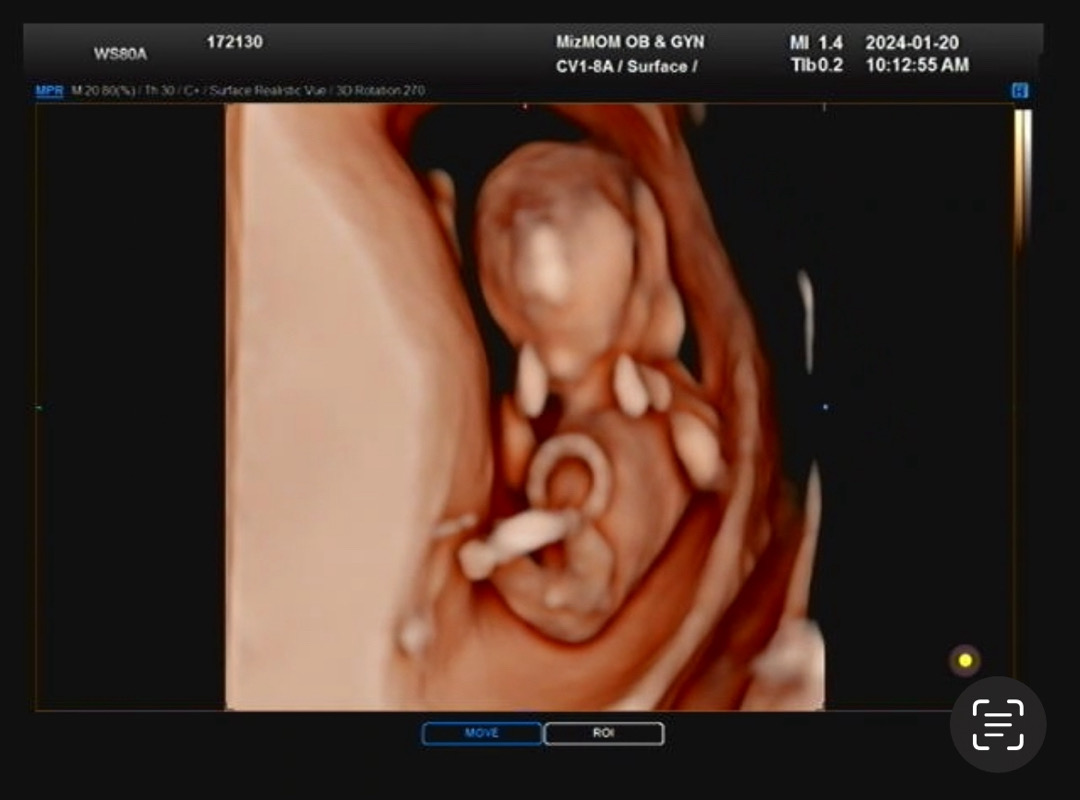

입체초음파도 성별 봐주세용~!

12쥬 0일인데 입체초음파에서 이렇기 나왔는데 아직 모르는 시기라고 하던데 어떨것 같나용???